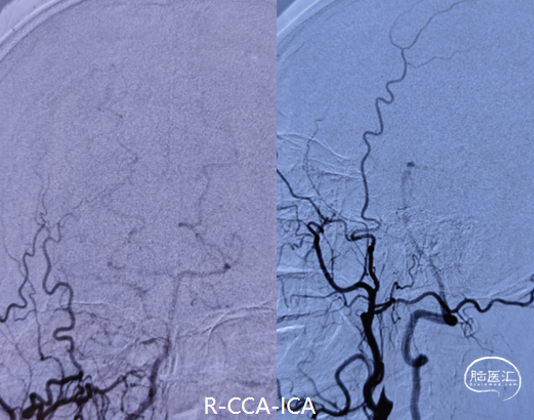

DSA造影(2024.11.07)

右侧颈内动脉起始段闭塞,动脉晚期可见颈动脉颅内段浅淡显影。

前交通动脉开放,右侧大脑中动脉显影良好。